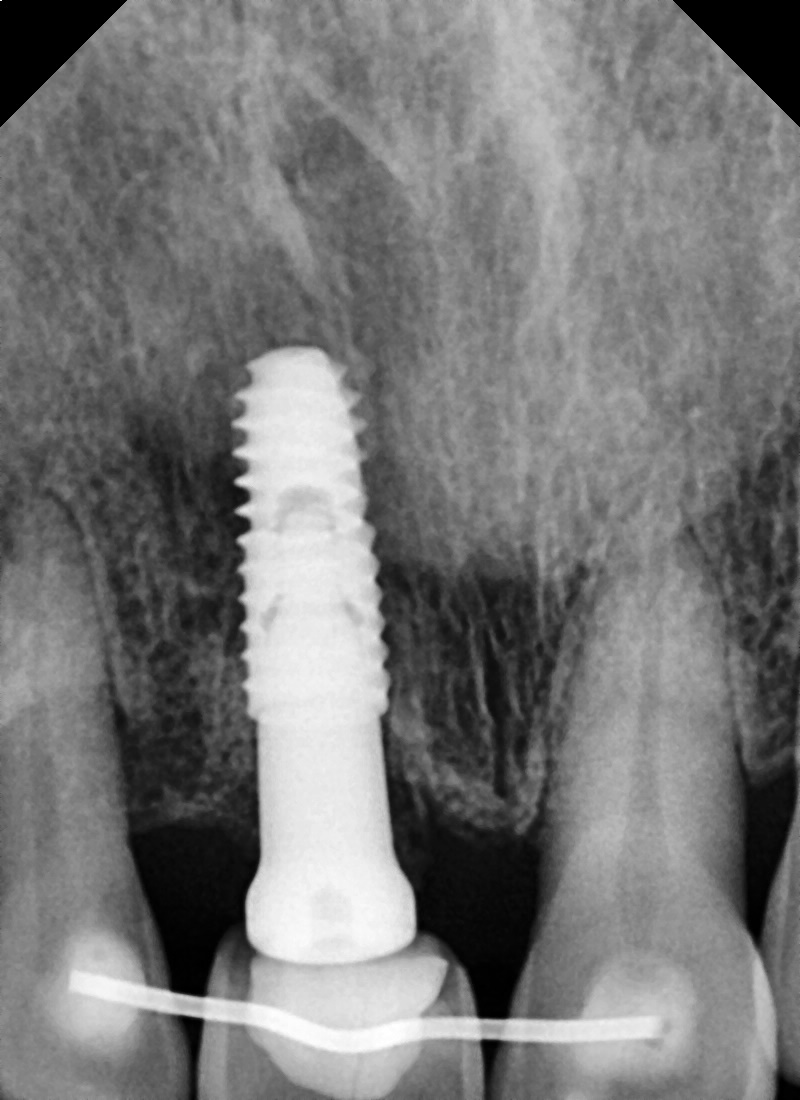

엑스레이 사진에서와 같이 발치된 치아를 와이어에 붙여서 양쪽 치아에 2~3달 정도 고정을 시켜주게 됩니다.

임플란트가 식립되어 있는 상방에 발치된 치아를 다듬어 임플란트에 자극을 주지 않게 했습니다.

이런 경우는 이렇게 공간이 크지 않거나 아래 치아에 걸리지 않는 경우 시도해 볼 수 있는 경우입니다.

일반적으로 앞니 부분의 잇몸뼈는 약하기 때문에 임플란트와 주변골과 초기 고정이 약하거나

다수의 치아를 발치하고 수술하는 경우는 대부분 임시틀니 같은 가철성 장치를 사용합니다.